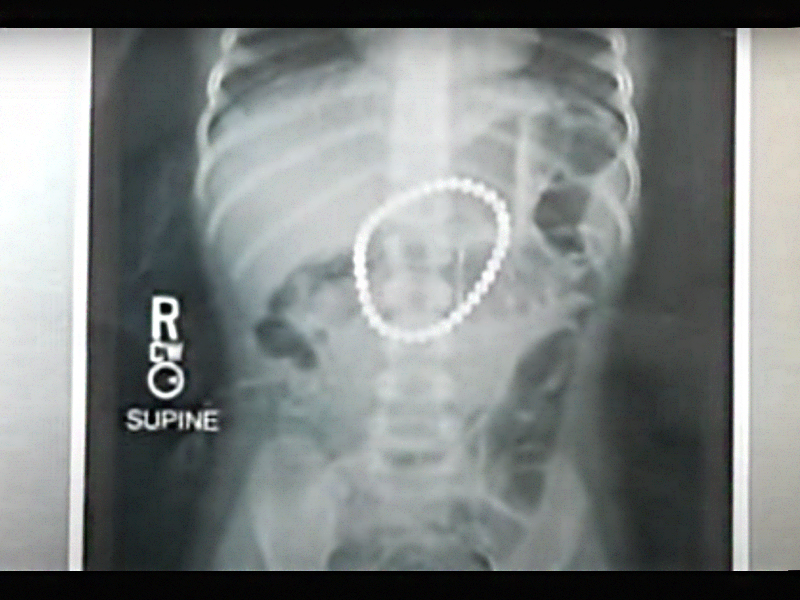

Egy hároméves kislány röntgenfelvétele, aki 37 mágnesgolyót nyelt le - forrás: Youtube

Ha tehát a kezdeti röntgenfelvétel többszörös mágnes-idegentestet igazol, akkor nem elégséges az ambuláns ellátás, hanem kórházi megfigyelés szükséges gyermeksebészeti osztályon, mert csak így biztosítható, hogy az alattomos szövődményeket időben felismerik.

Ha szükséges, itt naponta is lehet újabb röntgenfelvételt készíteni, amivel az idegentestek haladását lehet követni. A döntő azonban a gyermek állapotának, hasi státuszának folyamatos nyomon követése, így a körülírt hashártyagyulladás is azonnal felismerhető és még kezdeti stádiumban be lehet avatkozni.